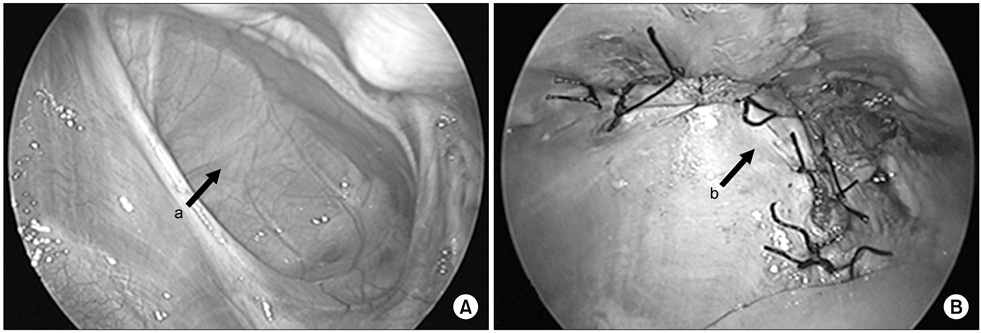

Fig. 6

Congenital diaphragm hernia. (A) There was hernia sac on right diaphragmatic defect. (B) Hernia sac was excised and primary repair was performed. Arrows: a, hernia sac; b, primary closure.

Fig. 6 Congenital diaphragm hernia. (A) There was hernia sac on right diaphragmatic defect. (B) Hernia sac was excised and primary repair was performed. Arrows: a, hernia sac; b, primary closure.